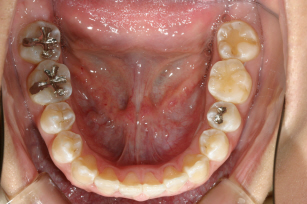

下顎前歯が翼状捻転しています。

下顎もバッチリ改善しています・